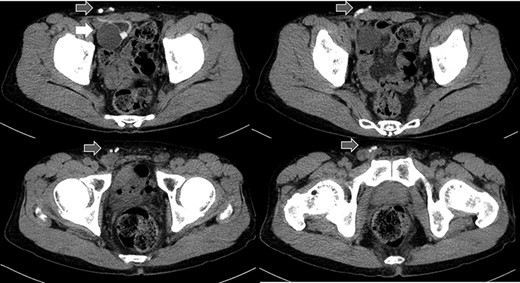

Abdominal CT in Case 1: CT showed that there was a balloon nearby the bladder and the tube went beside the rectus abdominis muscle from abdominal cavity; balloon, white arrow; tubes, gray arrows.

A 79-year-old male was referred to our institute for the treatment of right IH. He had received AUS implantation for the treatment of incontinence after RP for prostate cancer. Abdominal

computed tomography (CT) showed right IH and a balloon that was placed by the bladder and a connecting catheter that went through the lateral side of the rectus abdominis muscle (Fig. 2). In the operation, we performed ultrasonography (US) at first and it demonstrated that the catheter was running through the inguinal canal (Fig. 3). When we incised the aponeurosis of the external abdominal oblique muscle, the catheter of the AUS was observed in the inguinal canal (Fig. 4). We identified the hernia sac protruding from the inguinal ring and diagnosed it as an indirect IH. The adhesion was too hard to separate the catheter from the pubis and posterior wall of the inguinal canal around pubis. Then, the IH was repaired using the Lichtenstein technique; however, the mesh near the pubis could not be spread as ordinarily.